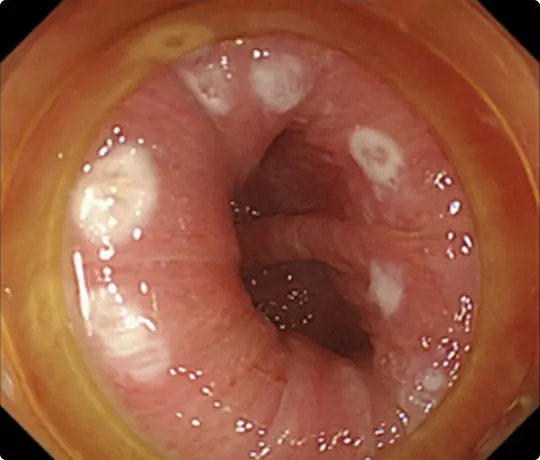

黄色い矢印で示す部分が少し赤くなっています。この部分が咽頭癌です。非常に分かりにくい病変です。

ヨードと呼ばれる薬液で染色すると、白い矢印で示す部分に咽頭癌(周りと色の違う部分)が浮かび上がってきます。

咽頭癌を取り囲むように、電気メスで白いマークを付けました。治療の際の目印になります。